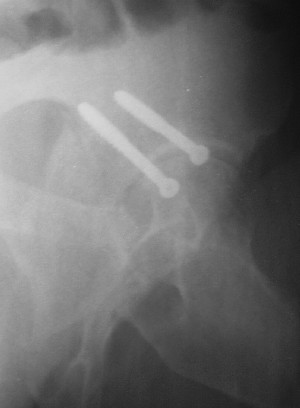

После протезирования прямой 5/04/04

|

Больной 18 мая 2003 года в автоаварии получил перелом левой вертлужной впадины, вывих бедра. Госпитализирован в один из стационаров области.Вывих вправлен. В последствии бедро вывихивалось еще дважды. На консультацию был представлен снимок от 19.05.03г., больной переведен к нам 3.06.03г. Снимок при поступлении - перелом впадины, задне-верхний вывих бедра. 05.06.2003 г. выполнено открытое вправление вывиха левого бедра и остеосинтез стенки вертлужной впадины двумя винтами. Послеоперационный период без осложнений. Объем движений в левом тазобедренном суставе восстановился полностью. Выписан на амбулаторное лечение в удовлетворительном состоянии с рекомендациями 3 месяца ходить на костылях без нагрузки на оперированную конечность. На контрольных рентгенограммах левого тазобедренного сустава 13.10.2003 г. - признаки консолидации перелома; плотность, форма головки и состояние суставных поверхностей удовлетворительные. Разрешена дозированная осевая нагрузка, на конечность с использованием дополнительной опоры. 19.12.2003 г. больной обратился с жалобами на боли в левом тазобедренном суставе. На рентгенограммах левого тазобедренного сустава 19.12.2003 г., 20.02.04г. - асептичекий некроз головки бедра. 5.04.04г. - эндопротез. Сейчас ходит без трости, не хромает. Особенность эндопротезирования - при удалении винтов прослежена линия перелома заднего края впадины и предложено установить чашку несколько меньшего диаметра, чтобы она была покрыта несломанной частью.